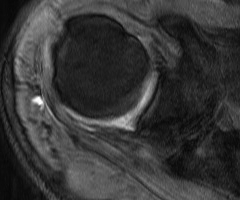

MRI

Inflammation and thickening of the rotator cuff tendons

Mild inflammation of the supraspinatus tendon insertion

Thickening and edema of the supraspinatus and infraspinatus tendon

Subscapularis tendinosis